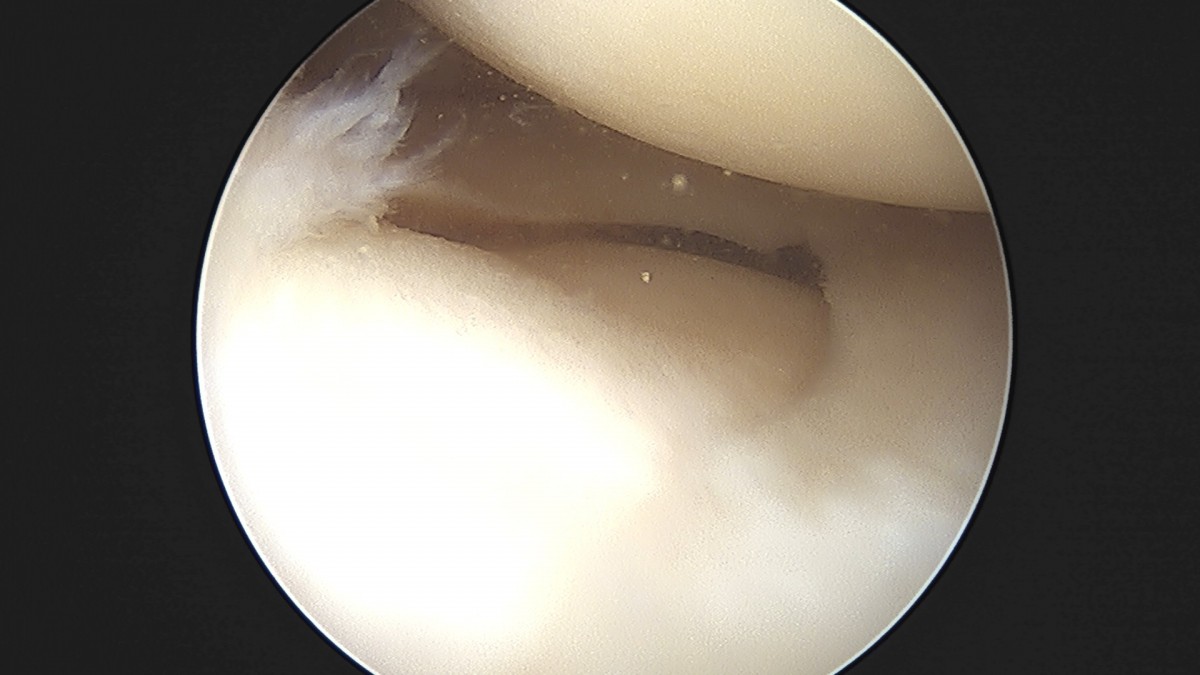

이재상원장님 무릎 반월상 연골판 절제술 조미O 환자

작성자 최고관리자 댓글 0건 조회 368회 작성일 25-09-16 16:01